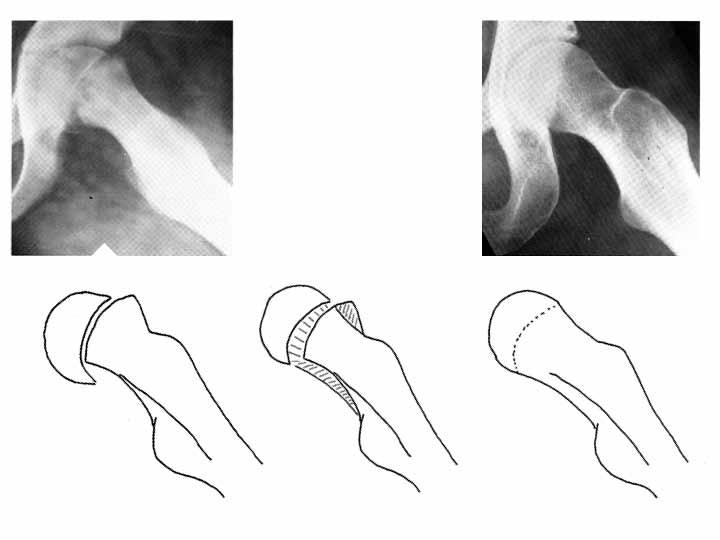

Vilka faktorer spelar roll vid val av ocementerad cup respektive stam baserat på de implantat som för närvarande används i Sverige?

Generellt sett är det inga stora generella skillnader i utfallet mätt som revision mellan val av ocementerad cup. Riskprofilen för uppkomst av olika komplikationer som kan leda till revision är dock olika. Upp till cirka 70 år är risken för revision på grund av lossning/osteolys något reducerad vid användning av ocementerad cup men dessa implantat drabbas å andra sida av andra komplikationer, vilket innebär att risken för revision blir relativt lika. På äldre patienter (70 år och över) bör man använda cementerad cup som förstahandsval.

I klinisk praxis bör man överväga ocementerad fixation om det är svårt att uppnå en god interdigitation mellan cement och trabekulärt ben. Detta kan inträffa om acetabulum är sklerotisk eller om kvaliteten på det trabekulära benet är dålig vilket ofta är fallet vid OA sekundär till CDH.

Generellt sett är cementerad stam associerad med färre revisioner under de första åren postoperativt. Efter cirka 7-10 år sker en utjämning så att protesöverlevnad blir ungefär lika. Orsaken är att ocementerade stammar under de första postoperativa åren drabbas av ökad risk för revision på grund av periprostetisk fraktur och lossning.

Efter cirka 10 år är risken för revision på grund av lossning mindre om man använder en ocementerad stam. Detta gäller framför allt yngre patienter. Hos äldre bör man undvika användning av ocementerad stam eftersom risken för tidig periprostetisk fraktur och lossning är ökad.

I klinisk praxis kan man överväga ocementerad stam hos patienter med god benkvalitet och hög aktivitetsnivå. Detta gäller speciellt patienter med tjockt kortikalt ben och smal märghåla. Om det föreligger sekundära tecken på osteoporos som till exempel en vid märghåla med tunn kortex bör man använda cementerad stam oavsett ålder.

Valet av cementerad eller ocementerad stam eller cup påverkas också av kirurgens vana med respektive proteskoncept. Dessutom spelar det också roll vilken typ av cementerad stam som man har tillgänglig.